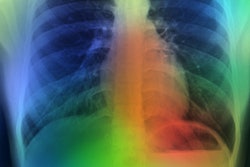

Occlusion maps identifying key features in representative chest x-rays with high and low diagnostic scores. Dark green pixels highlight significant features for model prediction, primarily associated with cardiomediastinal, upper abdominal, lower neck, and supraclavicular regions. Examples of CXRs with high and low diagnostic scores are presented. Image and caption courtesy of Nature Communications through CC BY 4.0.

Occlusion maps identifying key features in representative chest x-rays with high and low diagnostic scores. Dark green pixels highlight significant features for model prediction, primarily associated with cardiomediastinal, upper abdominal, lower neck, and supraclavicular regions. Examples of CXRs with high and low diagnostic scores are presented. Image and caption courtesy of Nature Communications through CC BY 4.0.The prospective test dataset of 9,943 images included 8,382 (84.3%) patients with no type II diabetes, 1,119 (11.3%) who had controlled disease, and 442 (4.4%) with poorly controlled disease. According to the findings, the model effectively detected type II diabetes with an area under the receiver operating curve (AUC) of 0.84 and a 16% prevalence. The model flagged 1,381 cases (14%) as suspicious for type II diabetes.

Finally, the authors noted that the occlusion maps generated to display the basis for the DL model's decisions corresponded significantly to known fat distribution features for the disease in the central chest, lower neck, upper abdomen, and axillary regions.